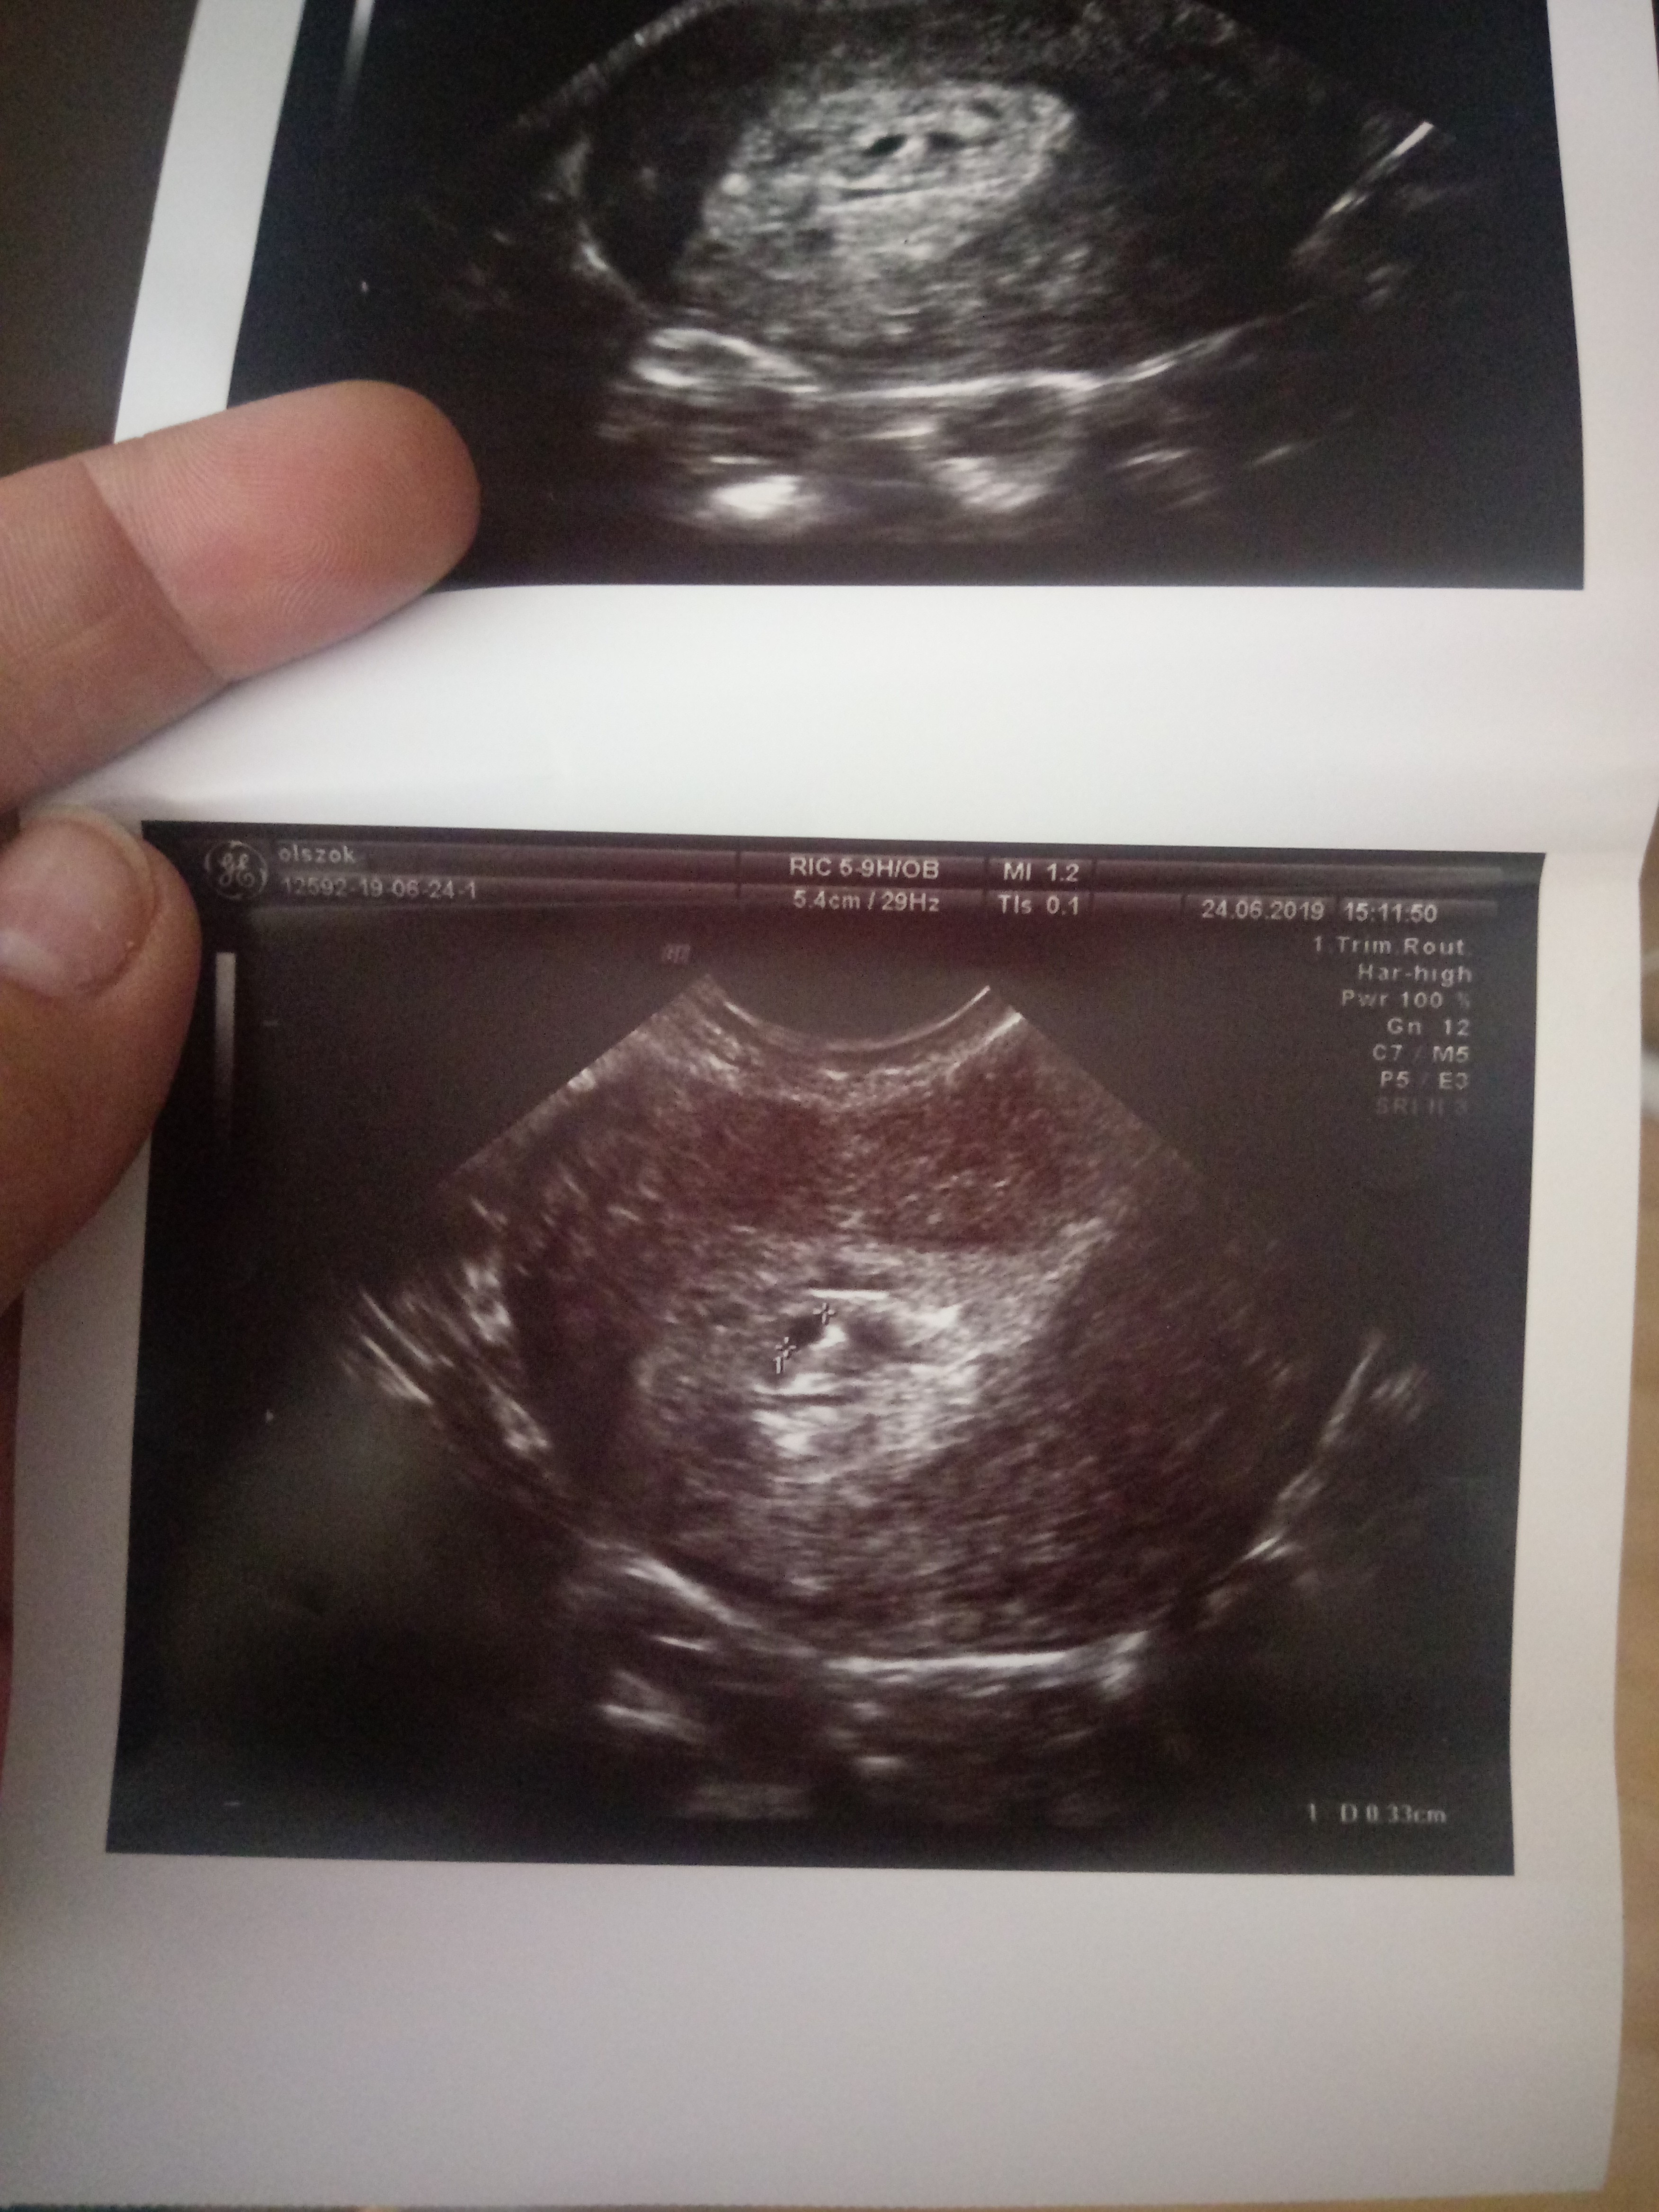

Czy ten przyrost jest ok ?

Pomocy. Dziś byłam u gin i ogólnie pęcherzyk jest ale mały obok jakieś plamy. Beta przez tydzień urosla mi z 54 do 903. Do tego po tym badaniu mam jakiś lekko naprawdę lekko różowy śluz. Kurcze martwię się :(

Przyrost wg mnie w porządku. Jeżeli lekarz nic więcej nie mówił, to myślę, że nie ma co się martwić na zapas. Dużo odpoczynku, mało nerwów i będzie w porządku [emoji6]

A który to tydzień ? przyrost wydaję się ok , wiesz te plamki to mogą być krwiaki , ja miałam taki jeden , ale brałam i nadal biorę polocard i się wchłonął lub wyleciał , bo 2 razy miałam jednorazowe plamienie , to że coś leci może być przez badanie , a co dokładnie powiedział Ci lekarz ? zlecił jakieś badania?? kazał coś brać jakieś leki ?